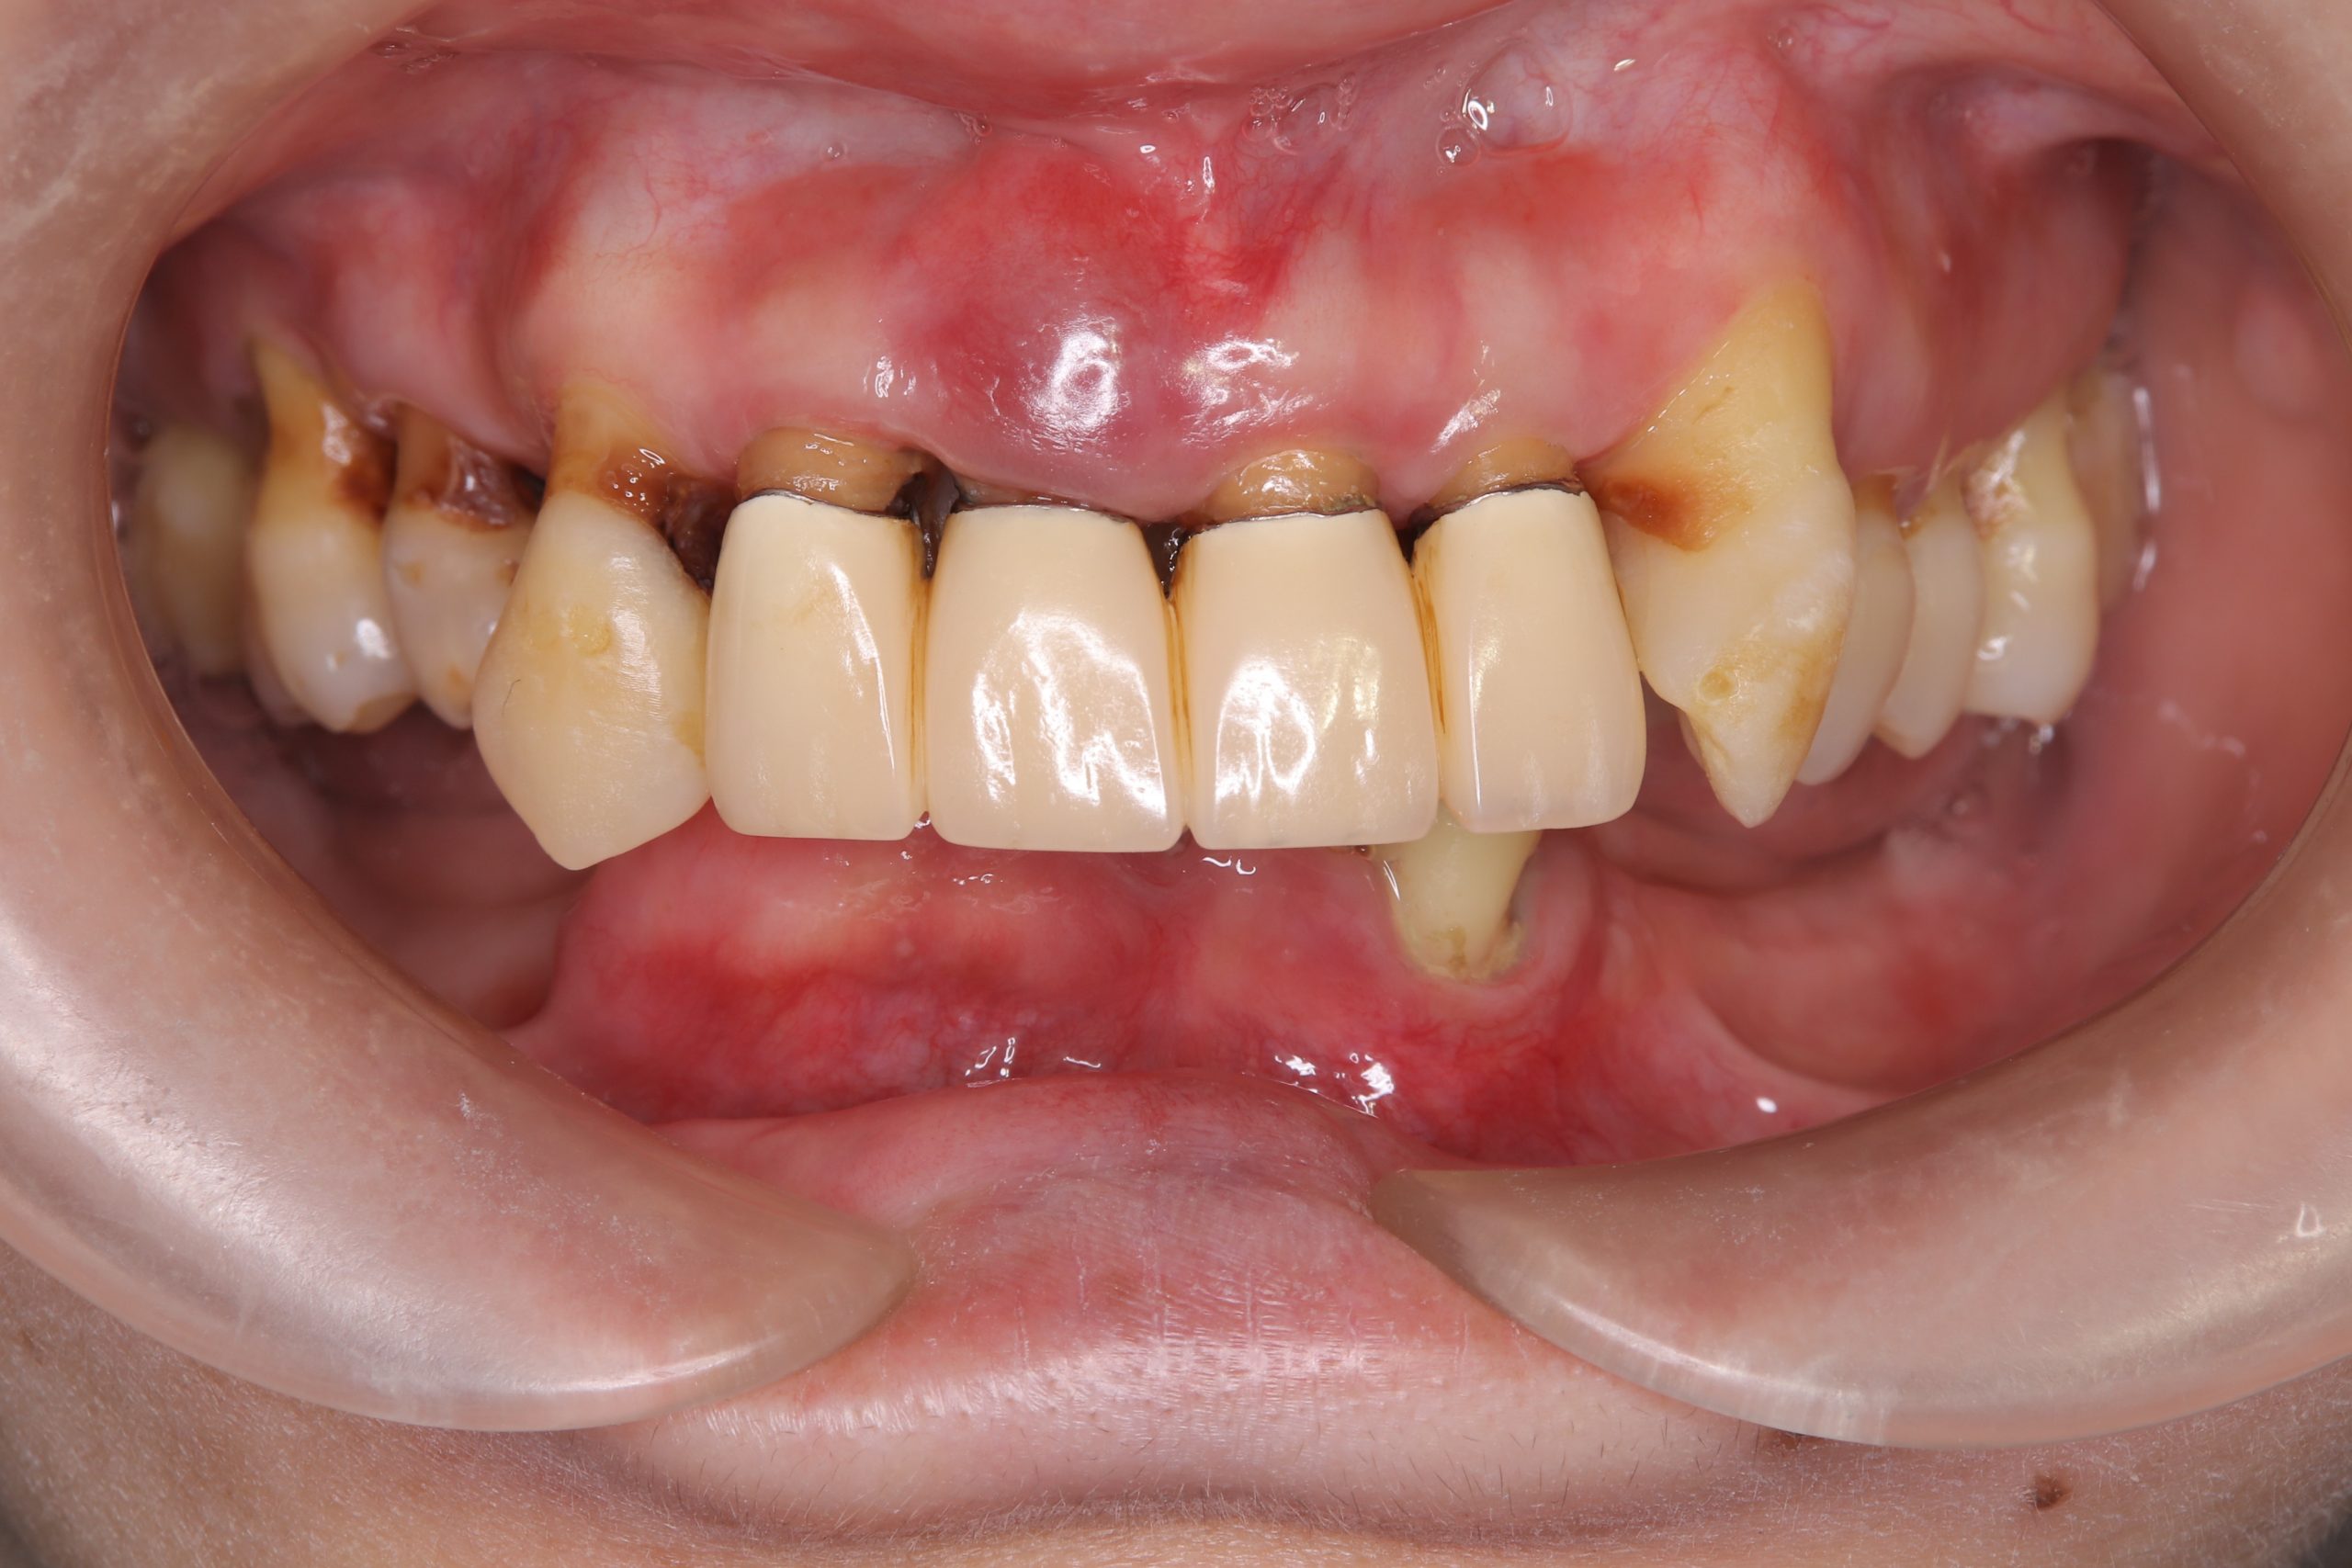

患者さんは、40代で既に重度歯周病に罹患している患者さんです。

この患者さんも、歯周病がかなり進行し、歯を支えている骨は残っておらず、抜歯せざるを得ない歯が多くありました。

この患者さんの場合、上顎においては数本の歯がなんとか残せる状態でした。